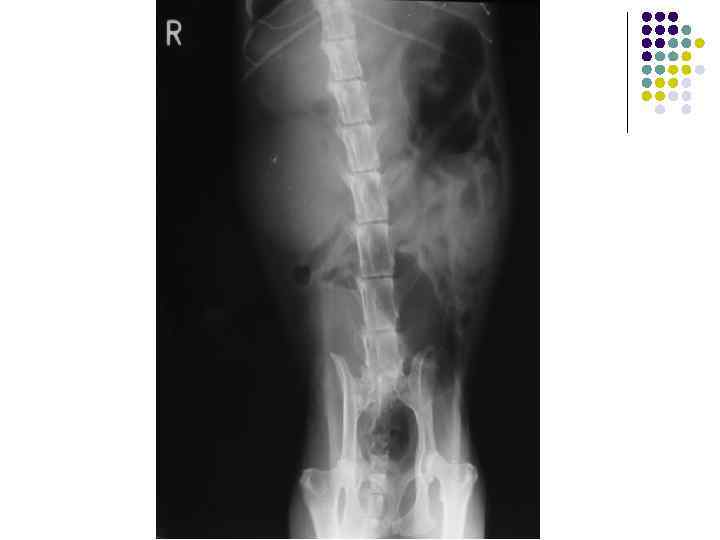

Уменьшенные почки у кота

Х. П. Н.